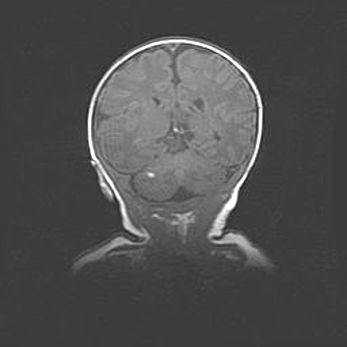

Множественные кисты обоих полушарий головного мозга, наибольшая из них в правой затылочной области. Ассиметричная атрофическая гидроцефалия.

Возраст: 7 месяцев

Вес: 5660 г

Пол: мужской

Окружность головы: 41,5 см

Срок гестации: 28-29 недель

Кисты головного мозга развиваются в результате многоочаговых некрозов вещества мозга и возникают вследствие перенесенной перинатальной инфекции, менингитов, энцефалитов, асфиксии, родовой травмы, расстройств мозгового кровообращения различного генеза. Образованию кист в веществе головного мозга плодов и новорожденных способствуют такие факторы, как высокое содержание в нем воды, недостаточная (или отсутствие) миелинизация и слабая астроглиальная реакция на повреждение.

Кисты могут сочетаться с гидроцефалией и другими поражениями головного мозга.